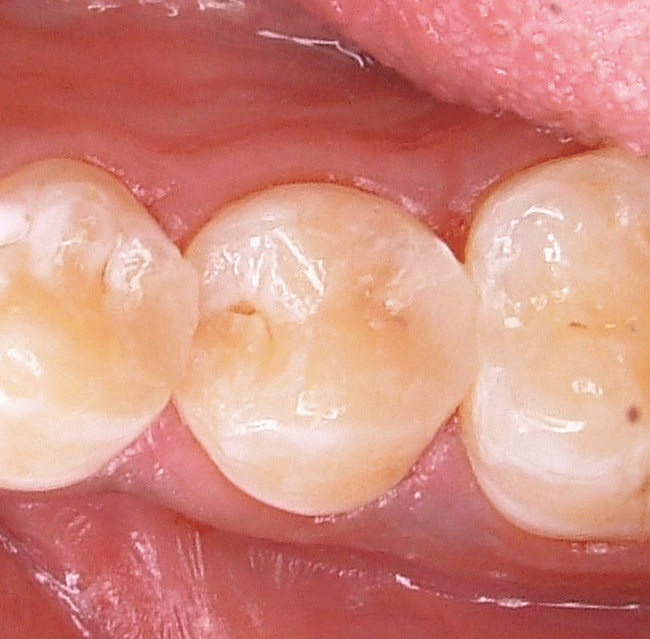

Finishing and polishing posterior composite resin restorations follow the same principles as those for anterior composite resin restorations, with one exception. Because these restorations are not in the esthetic zone (ie, do not need to be highly lustrous when dry), they can be polished to a smooth finish that is indistinguishable to the patient from the tooth being restored when the patient rubs his or her tongue over the tooth/restoration surface. The restoration is smooth, but not shiny. For example, Figure 8 shows distal caries in a mandibular premolar. Once restored, the restoration will need to be finished and polished. As with anterior composite resin restorations, use a finishing bur (Figure 9) or ultrafine finishing diamond to marginate and shape the restoration. Then polish the surface of the restoration with either composite resin rubber (silicone) polishers (Figure 10) or specialized polishing brushes (Figure 11). A new generation of abrasive-impregnated polishing brushes is available in a variety of shapes and sizes that can be used for almost every posterior composite resin surface. These new brushes have become the composite polishers in these authors' armmentaria. Using these brushes in a right-angle-latch handpiece leaves no mess after finishing and polishing in one step. Even without creating a high luster, this finishing sequence produces a completed restoration with a high esthetic appeal (Figure 12). As with any posterior restoration, after finishing and polishing, the clinician must verify and adjust any occlusal discrepancies.

Figure 8  Preoperative view of mandibular pre-molar with distal caries.

Figure 12  Completed posterior composite resin restoration.